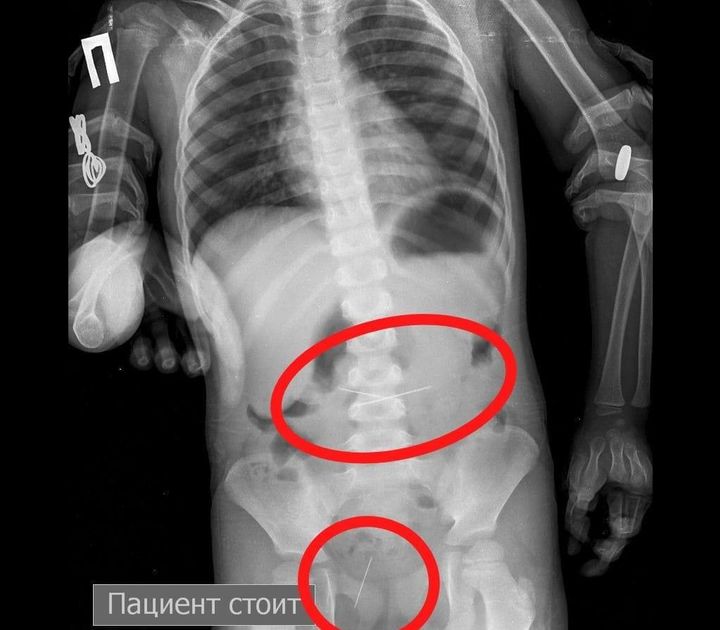

"Sputnik Kazaxstan" xabar berishicha, ona 3 yoshli farzandini kasalxonaga olib kelgan. Rentgenda bolaning oshqozonida 4 ta tikuv ignalari borligi aniqlangan.

Shifokorlar bir necha kun davomida endoskopik asbob-uskunalar yordamida jarrohlik amaliyotisiz ignalarni olib tashlashgan. Hozirda bolaning ahvoli yaxshi va uyiga ruxsat berilgan.